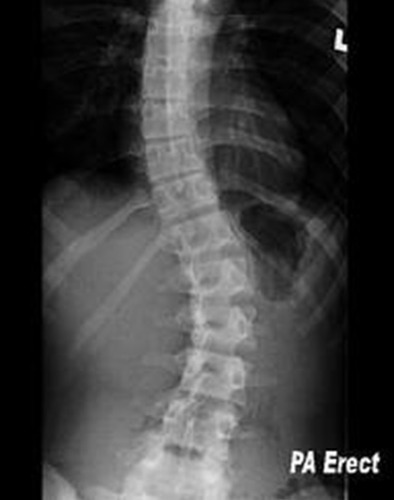

scoliosis

from lack of proper development of one vertebrae; left to right curve